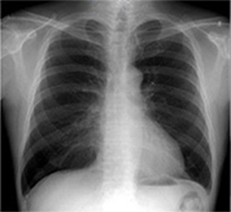

胸部経時差分処理

Temporal Subtraction処理

Temporal Subtraction処理は、独自のアルゴリズム補正をもとに、胸部画像の現在と過去の差分画像を生成する画像処理技術です。

そこで、現在と過去の差分画像を生成し「変化の有無」を可視化することで、診断精度の向上と時間短縮が期待でき、胸部読影を強力にサポートします。

◆変化が可視化され、新規病変の認識がしやすくなる。

◆肺門部や心臓裏の見落としやすい部位の病変が見つけやすくなる。

◆過去画像と現在画像の比較により経時的変化が画像化され、経過観察が容易になる。